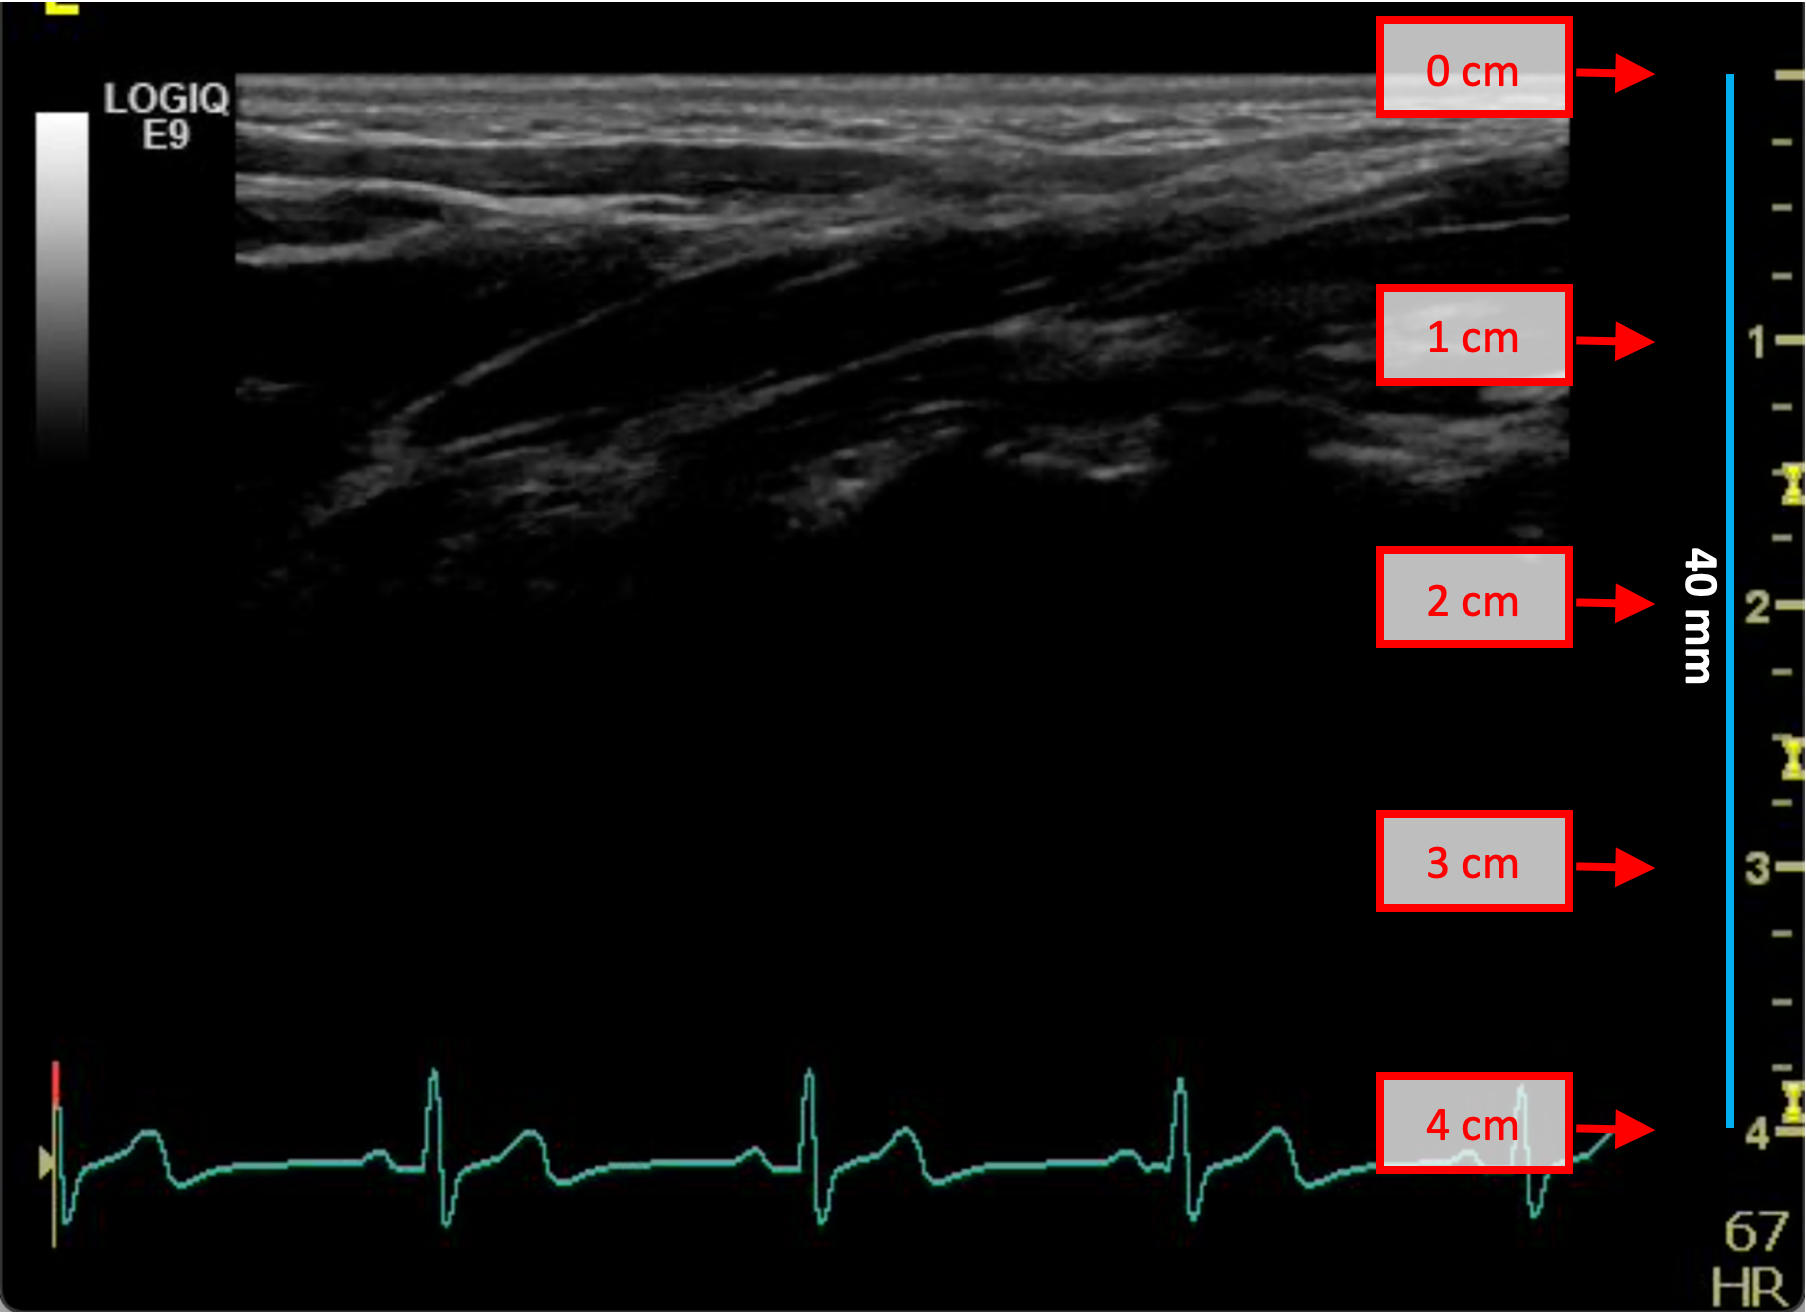

B-mode calibration examples

The following images show examples of calibrations of the b-mode image. Graphic items in red shows where you can find the information about the depth of the image in the ultrasound image.